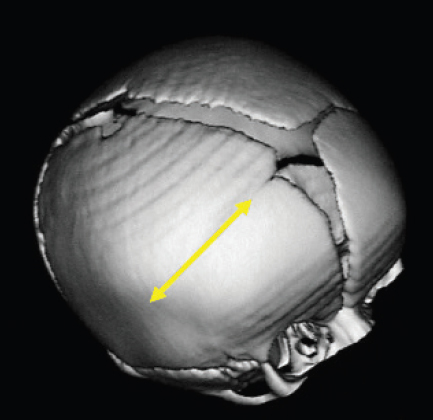

CHAPTER Normal skull growth and potential neurologic function may be affected by the presence of continued pressure in any one area of the cranium or by the presence of one or more pathologically fused cranial sutures. Posterior deformational plagiocephaly, most often secondary to a supine sleeping position, will generally resolve with positional changes, physiotherapy, or helmet therapy and is only rarely a surgical condition. The presence of a pathologically fused suture will produce deformity of the skull and is frequently an indication for operative release. The fused sutures determine the phenotype of the craniofacial deformity. According to Virchow’s Law, bone growth can no longer occur across (perpendicular to) the affected suture and therefore only occurs along it (parallel)1 (Fig. 41.1). Craniosynostosis can be classified into simple (single suture) versus complex (multiple sutures) and nonsyndromic versus syndromic subtypes. Assessment of an infant with an abnormal head shape includes a detailed medical history and physical examination to rule out a positional cause and identify any complicating sequelae. The medical history should identify any history of skull irregularities, associated syndromes, family history of calvarial deformities, and symptoms of intracranial hypertension (headache or vomiting, developmental changes, irritability, or oculomotor paresis). Often, parents note an abnormal head shape at the time of delivery or one that becomes more apparent later in infancy. Patients with irritability, feeding difficulties, failure to thrive, headache, developmental delays, visual changes, marked turricephaly, supraorbital recession, bulging or “tight” fontanels, abnormal distended scalp veins, or a lack of circumferential skull growth may have an increase in intracranial pressure. For patients with head shape abnormalities, a careful physical examination should be able to identify the cause. Positional deformation presents with a classic parallelogram appearance when looking from above. Skull deformation caused by premature fusion produces characteristic findings, including asymmetry (supraorbital retrusion, towering or turricephaly, frontal or occipital bossing), inability to palpate the anterior fontanelle (which normally remains open until 12 to 18 months of age), perisutural ridging, and signs of intracranial hypertension (papilledema). Studies have shown that the presence of intracranial hypertension is dependent on the number of affected sutures, ranging from approximately 14% for single-suture synostosis to approximately 47% in multisuture synostosis.2,3 Suture release in craniosynostosis is often offered to correct the craniofacial deformity and to address potential increased intracranial pressure that in some patients has resulted in blindness and developmental delay. Fig. 41.1 Virchow’s law: Bone growth can no longer occur across (perpendicular to) a fused suture and therefore only occurs along it (parallel). The specific calvarial shape can indicate which sutures are involved. Children with sagittal synostosis present with a narrow, elongated skull (dolichocephaly describes long-headedness; scaphocephaly describes a boat-shaped head). Depending on the region of greatest fusion of the sagittal suture, the child may manifest frontal or occipital bossing or a combination of both. Some children will also demonstrate a “towering” skull, also known as turricephaly. Metopic synostosis is marked by a variable degree of phenotypic severity, ranging from mild ridging to the formation of a triangular head (trigonocephaly) or prominent “keel” forehead with or without hypotelorism. Although an endocranial ridge is not commonly seen in patients with metopic synostosis, an endocranial notch can be observed on axial CT images and is virtually diagnostic of pathologic suture fusion. Patients with unicoronal synostosis present with anterior plagiocephaly, whereas those with bilateral coronal involvement demonstrate brachycephaly. Phenotypic features of anterior plagiocephaly include ipsilateral perisutural ridging, forehead flattening, and orbital recession, coupled with contralateral compensatory frontal bossing. Facial deformities are also common, including nasal root displacement toward the ipsilateral side, anterior displacement of the ipsilateral ear, and chin deviation toward the contralateral side, resulting in a classic C-shaped craniofacial deformity—concave contralateral to the fused suture. Children with lambdoid synostosis characteristically have a trapezoid-shaped head (seen from the vertex view) in association with posterior displacement of the ipsilateral ear, contralateral occipital bossing, ipsilateral mastoid bossing, and ridging of the affected lambdoid suture. In contrast, posterior deformational plagiocephaly is marked by a parallelogram-shaped head when viewed from the vertex, anterior displacement of the ipsilateral ear, ipsilateral frontal bossing in the absence of palpable lambdoid suture ridge, and no mastoid bossing as is seen with lambdoid suture fusion (Fig. 41.2). Posterior plagiocephaly caused by lambdoid suture synostosis is rare; the majority of posterior plagiocephaly is secondary to positional molding. Understanding the phenotypic differences between lambdoid synostosis and posterior deformational plagiocephaly is critical for making the appropriate diagnosis and designing the proper course of treatment. Head circumferences, cranial indices, and anthropometric measurements should also be noted. Imaging studies may be necessary to confirm the diagnosis and rule out any associated intracranial abnormalities. For younger patients, ultrasonography has been used as a screening tool to visualize the sutures through the open fontanelles. Although not as sensitive as computed tomography (CT), it avoids the risk of radiation exposure. CT remains the most sensitive modality to assess bony sutural fusion and may suggest elevated intracranial pressure, as noted by areas of erosion of the inner calvarial table (“copper-beaten” appearance) (Fig. 41.3). Pathognomonic for unicoronal synostosis, elevation of the ipsilateral orbit can be seen secondary to superior displacement of the greater wing of the sphenoid, also known as the “harlequin” deformity. Modern CT protocols attempt to minimize the radiation dose to the infant.4 Both CT and magnetic resonance imaging (MRI) are helpful in evaluating the underlying brain for structural or functional abnormalities, including hydrocephalus, holoprosencephaly, cortical dysplasias, and Chiari malformations. The latter are structural defects in the part of the brain that controls balance (cerebellum). Without sufficient space, the cerebellum and parts of the brain stem may sit too low, causing pressure and blocking the flow of cerebrospinal fluid. This is important to identify preoperatively, because intraoperative maneuvers may worsen the condition. Summary Box Common Complications in Synostosis Correction Intraoperative • Bleeding • Venous air embolism • Ocular injury and vision loss • Dural and brain injury, cerebrospinal fluid leak • Death Postoperative • Infection • Growing skull defects • Persistent calvarial defect • Hardware-related complication • Restenosis, relapse, growth restriction, and recurrence of deformity Surgical intervention is indicated in craniosynostosis to correct the craniofacial deformity and potentially treat or prevent functional disabilities believed to be secondary to intracranial hypertension (blindness, developmental de lay, psychosocial dysfunction). Patients with multisutural synostoses present with increased severity of physical and neurologic symptoms; therefore surgical intervention is even more important. The optimal surgical age has been debated, because the techniques of surgery are variable. Although the literature is inconclusive regarding the appropriate timing for correction of craniosynostosis, most craniofacial surgeons operate within the first year of age, taking into consideration the number and pattern of suture fusion, evidence of intracranial hypertension, and the surgical technique chosen. Minimally invasive techniques, which rely on less extensive craniotomies and external postoperative molding, are generally performed at an earlier age than are traditional open techniques. The technical portions of the procedures are complicated and have multiple risks. Avoidance of these risks is important to produce improved results. This begins with carefully evaluating potential patients preoperatively and optimizing their physical condition before surgery. In preparation for surgery, measures to ensure stable blood volumes should be undertaken. These include obtaining a baseline hemoglobin, blood type and crossmatch, and potential directed blood donation from a matched family member. Some surgeons use preoperative erythropoietin to minimize the need for transfusion.5 Surgery is performed under general anesthesia, which should be provided by a fellowship-trained pediatric anesthesiologist. Patients should be monitored postoperatively in an intensive care unit under the direction of pediatric critical care–trained physicians. A broad range of surgical options has been proposed for the surgical treatment of craniosynostosis. The goal of each is to remove the affected suture and either immediately remodel the remaining calvarial vault or provide postoperative guidance (distractors, springs, helmets) to allow this to occur. For most types of craniosynostosis repairs, patients are placed in the supine position to facilitate exposure. However, if the posterior vault is being addressed, as in a lambdoidal synostosis or some sagittal synostoses, the patient may be placed in the prone or sphinx position . In the prone position, care must be taken to ensure proper positioning with adequate protection of the eyes. Injury to the globe is devastating and should be a “never event.” Before the procedure begins, lubrication should be placed over the corneas; some surgeons approximate the eyelids with either adhesive tapes or formal tarsorrhaphy sutures that can be removed at the conclusion of the procedure. If the patient must be in the prone position, the face can be supported with a foam pillow or horseshoe headrest, with the eyes uncompressed within the opening of the support. Venous air embolism (VAE) is the introduction of air or gas from the operative field into either the arterial or venous vasculature and is a potentially fatal complication of neurosurgical procedures.6 Previous studies have suggested that the rate of VAE may be as high as 80% during such procedures. This may be lower for endoscopic techniques.7 Some believe that real-time monitoring, to identify the presence of a venous air embolism and allow for immediate intervention, mitigates the risk. Despite the introduction of newer diagnostic techniques, use of a precordial Doppler remains a standard modality. Although transesophageal echocardiography is the most sensitive method of detection,8,9 it is more costly and invasive. When properly placed between the third and sixth intercostal spaces along the right parasternal border, a precordial Doppler is potentially capable of identifying VAE at an air infusion rate as low as 0.015 mL/kg/min and consistently at a rate of 0.021 mL/kg/min.10,11 VAE may be graded by severity: change in Doppler tones (grade I), change in Doppler tones and decrease in end-tidal carbon dioxide (grade II), or decrease in systolic blood pressure by 20% from baseline (grade III). The calvarium is often approached via a standard “stealth” (zigzag) coronal incision, providing for adequate exposure while minimizing any postoperative scar. Perioperative antibiotics and steroids may be administered before the procedure. The incision is infiltrated with 1:200,000 epinephrine in 0.5% lidocaine to minimize bleeding along the incision site. The frontal and temporal regions are dissected in the subgaleal plane, and care is taken to preserve the periosteum on the surface of the bone, which helps minimize blood loss and may be used to stabilize the bony segments. Bleeding can occur at several points in the procedure. Incisions into the scalp can produce significant bleeding in the infant. This bleeding can be controlled with metal clips and cautery. Bleeding can also occur with elevation of the coronal flap. This is usually greater with subperiosteal dissection rather than supraperiosteal dissection. With either, punctate bleeding should be controlled with pinpoint cautery or bone wax. The latter should be used judiciously, because any wax left behind can serve as a nidus for infection. To “turn down” or reflect the coronal flap, the supraorbital vessels must be released from their attachments to the frontal bone. Sometimes, the vessels exit the bone through a notch; in older children they exit through a foramen. If the surgeon is not careful of these vessels, unnecessary bleeding can occur. When the vessels may exit through a foramen, a 2-mm osteotome should be used to convert the foramen to a notch by removing the inferior portion with the bony foramen. The vessels within the underlying periorbita can then be carefully dissected away from the bone. Performing the craniectomy involves making several small access holes and joining them with a side-cutting craniotome with a protective footplate. The access holes are made with a high-speed burr. Injury may occur if the burr is used too aggressively to enter the calvarial vault. The burr is often used to traverse the outer table, diploic space, and a portion of the inner table. As the remaining bone becomes thin enough, the burr can be put aside and communication to the epidural space made with a fine curette. Once a small opening is made with the curette, a Kerrison rongeur can be used to widen the opening further. The Kerrison has a protective footplate to minimize dural injury. Once the opening is large enough, a small elevator, such as a No. 4 Penfield, can be used to dissect beneath the bone and above the dura along the proposed craniotomy path. Once the bone cuts have been made, the bone flap should be removed carefully to avoid additional trauma to the underlying dura from sharp edges. The most severe bleeding can occur if there is injury to the sagittal sinus. The sagittal sinus is most at risk when the craniotome passes across the midline. For this reason, any cuts traversing the sagittal sinus are performed last. In the event of significant bleeding, the bone flap can then be removed relatively quickly to address the blood loss. With the remaining bone cuts already performed, the bone flap can be removed relatively quickly and any bleeding controlled. Injury to the sagittal sinus more posterior in the skull is more worrisome. The earliest approaches to treating craniosynostosis included simple suturectomy, allowing the brain to direct skull growth through the remaining open sutures. Inadequate correction prompted more extensive procedures of calvarial remodeling, and these have yielded improved results. These current techniques include wide scalp dissection, more remote calvarial osteotomies, and skull remodeling that is individually tailored to each cranial vault deformity.12 For sagittal synostosis, the surgical approaches range from minimal removal of the involved suture (usually combined with postoperative use of springs, distractors, or helmets) to extensive total calvarectomy and reconfiguration. Simple synostectomy, or simple strip craniectomy, when combined with postoperative springs, distractors, or helmet therapy, can be safe and well tolerated, providing adequate cosmetic results in select patients with mild deformities. Disadvantages include its lack of specifically addressing the severe compensatory changes in skull shape that result from the fused suture. It also leaves a large unprotected area over the vertex of the skull, an area with a high rate of restenosis and renewed growth restriction. The midvault “expanded strip craniectomy” provides a more immediate reconstruction of skull contour by shortening the anteroposterior dimension, expanding the biparietal dimension, and partially addressing the frontal and occipital prominences. The “Pi reconstruction,” a version of a midvault expanded strip craniectomy, is used for older infants (6 to 12 months of age) with scaphocephaly caused by sagittal synostosis (Fig. 41.4). Bone is removed lateral to the sagittal suture over the lateral parietal areas and molded, leaving two bony defects in the design of the Greek letter Pi (π). Cranial bone overlying the sagittal sinus is left intact to minimize bleeding. Axial compression is used to shorten and widen the skull, and absorbable plates are placed to hold the position. For coronal and metopic synostosis, the goal is to correct the frontal and orbital asymmetries. In the former, there is asymmetry in the shape of the orbits and forehead. In the latter, the typical deformity involves a midline ridge with retrusion of the supraorbital bar (“bandeau”) on either side of the forehead. The most common technique is fronto-orbital advancement (FOA). With an FOA, dissection continues within the orbits, freeing the periorbita off the upper half of the orbit. Caution must be taken to avoid injury to the underlying globes. To expose the roof of the orbits or anterior cranial base, a bifrontal craniotomy is marked and cut with an osteotome. Typically 1 to 2 centimeters of the superior orbital rim is left for support. The bone flap is placed aside and replaced in a more corrected position at the end of the procedure The supraorbital bar or bandeau is removed with careful osteotomies through the lateral orbit at the frontozygomatic suture, the superior orbit along the roof, and the nasion just above the nasofrontal suture. Care is taken to protect the underlying dura and brain as well as the orbital contents with adequate exposure and judicious use of retractors. This is a relatively low-risk maneuver but should similarly be performed with caution. The eyes are perhaps most at risk when cutting the orbital bandeau. Here, sufficiently wide malleable retractors should be placed between the globes and the saw blade or osteotome. The saw should not be run unless there is good protection of the underlying structures and the blade only advanced through the bone as far as needed. As the blade moves either medially or laterally, the retractors should follow to avoid inadvertent injury. The sphenoid wing is cut and the coronal sutures are opened to the level of the skull base to prevent continued growth restriction and resultant postoperative hollowing of the pterional regions. The bandeau is then reconfigured and fixed with resorbable sutures or plates and screws to maintain the newly contoured shape. Reconfiguration of the supraorbital bar might require osteotomies, both in the midline to flatten the forehead and laterally to normalize the lateral supraorbital angle. The goal is expansion on the affected side as well as recession on the contralateral side. When replaced, its lateral aspects and midline are fixed to the calvarial vault. This is performed for both unilateral and bilateral cases. To avoid relapse or a persistent deformity, overcorrecting the expansion of the affected side by 5 to 10% while also providing a convex shape at the lateral border is commonly necessary for a satisfactory reconstruction. The frontal bone flap is then attached to the supraorbital bar, taking care to match it to the previously overcorrected (5 to 10%) orbital bandeau on the affected side. For lambdoid synostosis, a variety of surgical approaches, aiming to release the affected suture(s) and normalize the posterior calvarial vault contour, have been described. Options include simple synostectomy, unilateral remodeling of the affected occipital region, and bilateral occipital reconstruction with or without the use of an occipital bandeau. Most lambdoid surgical candidates have significant parietal and frontal compensatory changes in addition to their occipital deformation; therefore they are best served by a more extended calvarectomy and remodeling. The reconstruction is similarly maintained with intervening bone grafts and resorbable hardware. Titanium was used early on but fell out of favor when it was noted that the plates translocated endocranially to the internal surface of the skull with calvarial growth. Resorbable plates made of polylactic acid provide temporary support across the osteotomy sites and dissolve within 12 to 24 months. After placement of the reconfigured supraorbital bar, the frontal bone is remodeled using the remaining portions of bone and fixed with absorbable plates or suture. Closure is performed in a routine fashion, with some surgeons placing subgaleal drains. To address concerns regarding incision length, operative blood loss, and length of stay associated with open cranio-facial procedures, minimally invasive techniques have been proposed. These techniques include endoscopic sutural release,13 spring-assisted cranioplasty14 (Fig. 41.5), and distraction osteogenesis15 (Fig. 41.6). Endoscopic release has been proposed to minimize the intraoperative risks by limiting the amount of bleeding from larger scalp incisions and bone flap elevation. The technique uses one or more small incisions, minimal dissection, and removal of the affected suture, possibly with adjunctive osteotomies into the surrounding bone. The technique does not attempt to completely correct the craniofacial deformity at the time of surgery but rather remove the offending sutures and allow remodeling during a period of postoperative brain growth, with or without external molding, or distractive force. The use of springs works in a similar fashion; the affected suture is removed and one or more internal springs are placed across the open osteotomy to guide remodeling of the skull (see Fig. 41.5). Of note, a second, smaller procedure is required to remove the springs. Similarly, distraction osteogenesis has been used to impart an internal force across the ostectomy site (see Fig. 41.6). New bone is laid down in the distracted osteotomy gap.